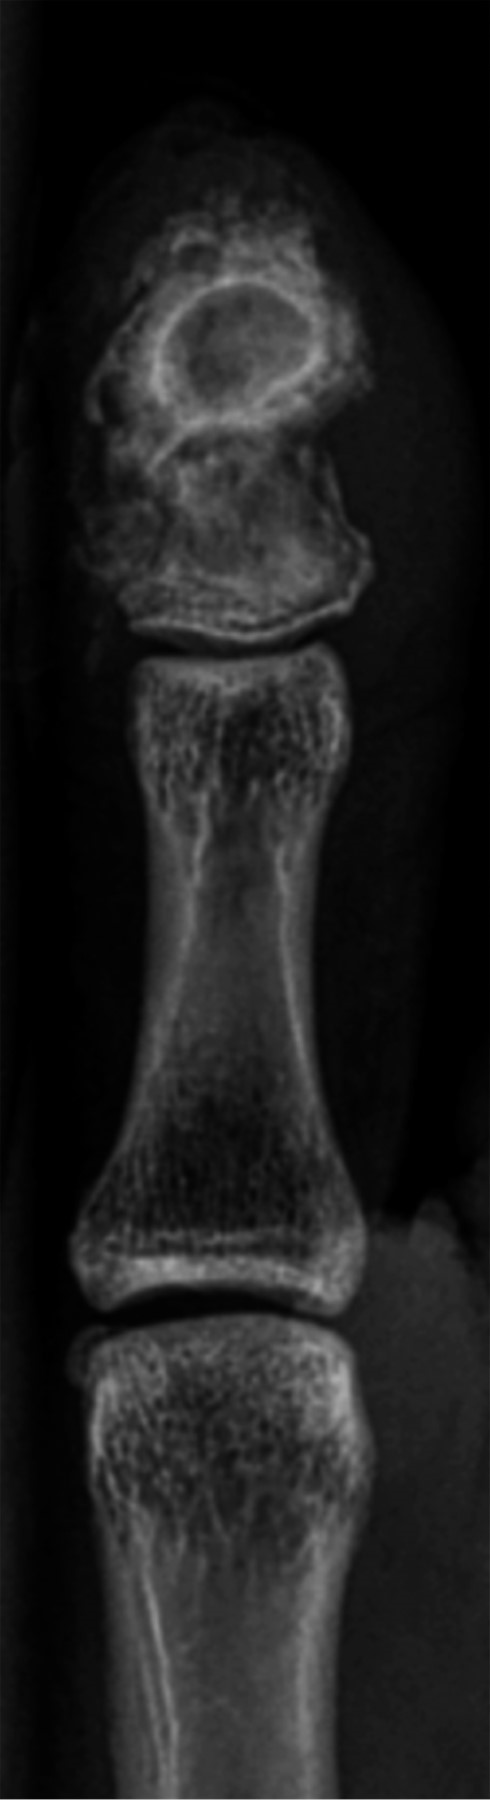

En la resonancia magnética nuclear (RMN) presentaba una ocupación medular completa de la falange, hipointensa con márgenes hiperintensos en T1, lo que es conocido como signo de penumbra. También presentaba reabsorción endóstica y rotura cortical. A nivel subcutáneo asociaba un leve edema sin presencia de colecciones ni afectación articular (Figura 1). Ante tales hallazgos se sugirió como primera opción diagnóstica la osteomielitis con un absceso subagudo y se programó la intervención quirúrgica.

Figura 1